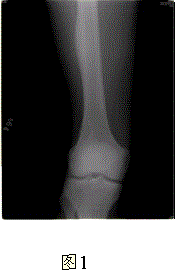

问题 患者男,17岁,右大腿外侧间歇性疼痛逐渐加重近3个月,夜间为重,X线片及CT示右股骨干下段外侧骨皮质梭形增厚硬化,增厚的骨皮质中心隐约可见小圆形低密度灶,骨髓腔未闭合,无外伤史(图1、2)。 与此病变相鉴别的疾病主要是